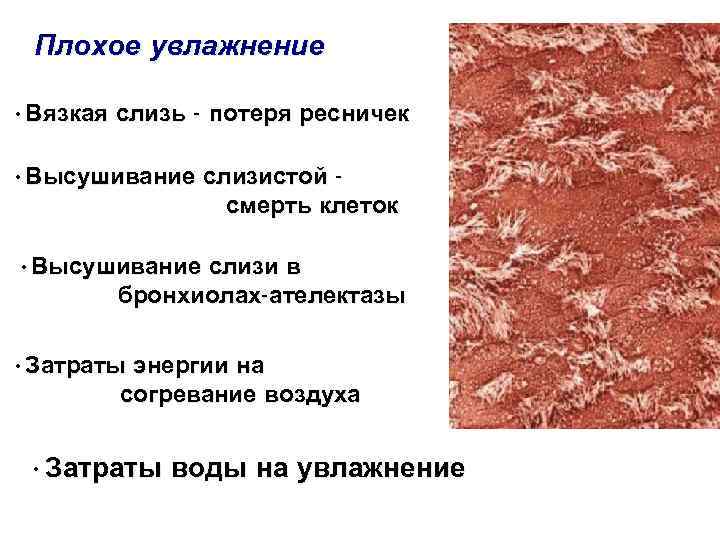

Факторы риска Недостаточное увлажнение дыхательной смеси Высушивание трахеи и бронхов

Факторы риска Недостаточное увлажнение дыхательной смеси Высушивание трахеи и бронхов

Плохое увлажнение • Вязкая слизь - потеря ресничек • Высушивание слизистой смерть клеток • Высушивание слизи в бронхиолах-ателектазы • Затраты энергии на согревание воздуха • Затраты воды на увлажнение

Плохое увлажнение • Вязкая слизь - потеря ресничек • Высушивание слизистой смерть клеток • Высушивание слизи в бронхиолах-ателектазы • Затраты энергии на согревание воздуха • Затраты воды на увлажнение